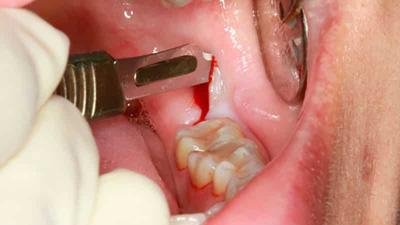

Фото 3. Атравматичное удаление без боли и длительного заживления. Благодаря данному способу становится возможным сохранение естественного рельефа десны.

Атравматичное: современный способ экстракции

Атравматичное удаление — современный метод, позволяющий провести процедуру экстракции зуба быстро и безболезненно. Проводится без использования щипцов под местной анестезией с применением препаратов последнего поколения, которые полностью лишают десну чувствительности.

Минус процедуры: высокая стоимость.

Плюсы:

- безболезненность;

- сокращается риск попадания инфекции в лунку;

- сокращается риск возникновения кровотечения;

- сохраняется естественный рельеф десны, так как межкорневая пластина остается нетронутой.